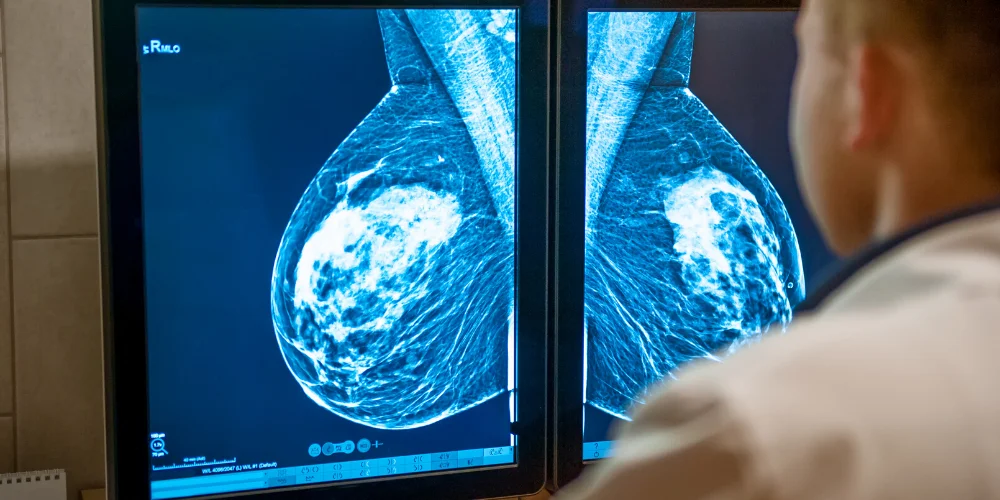

Digital mammography uses electronic detectors to capture and store X-ray images digitally.

Advantages: Improved image quality, easier storage, and faster retrieval for analysis.